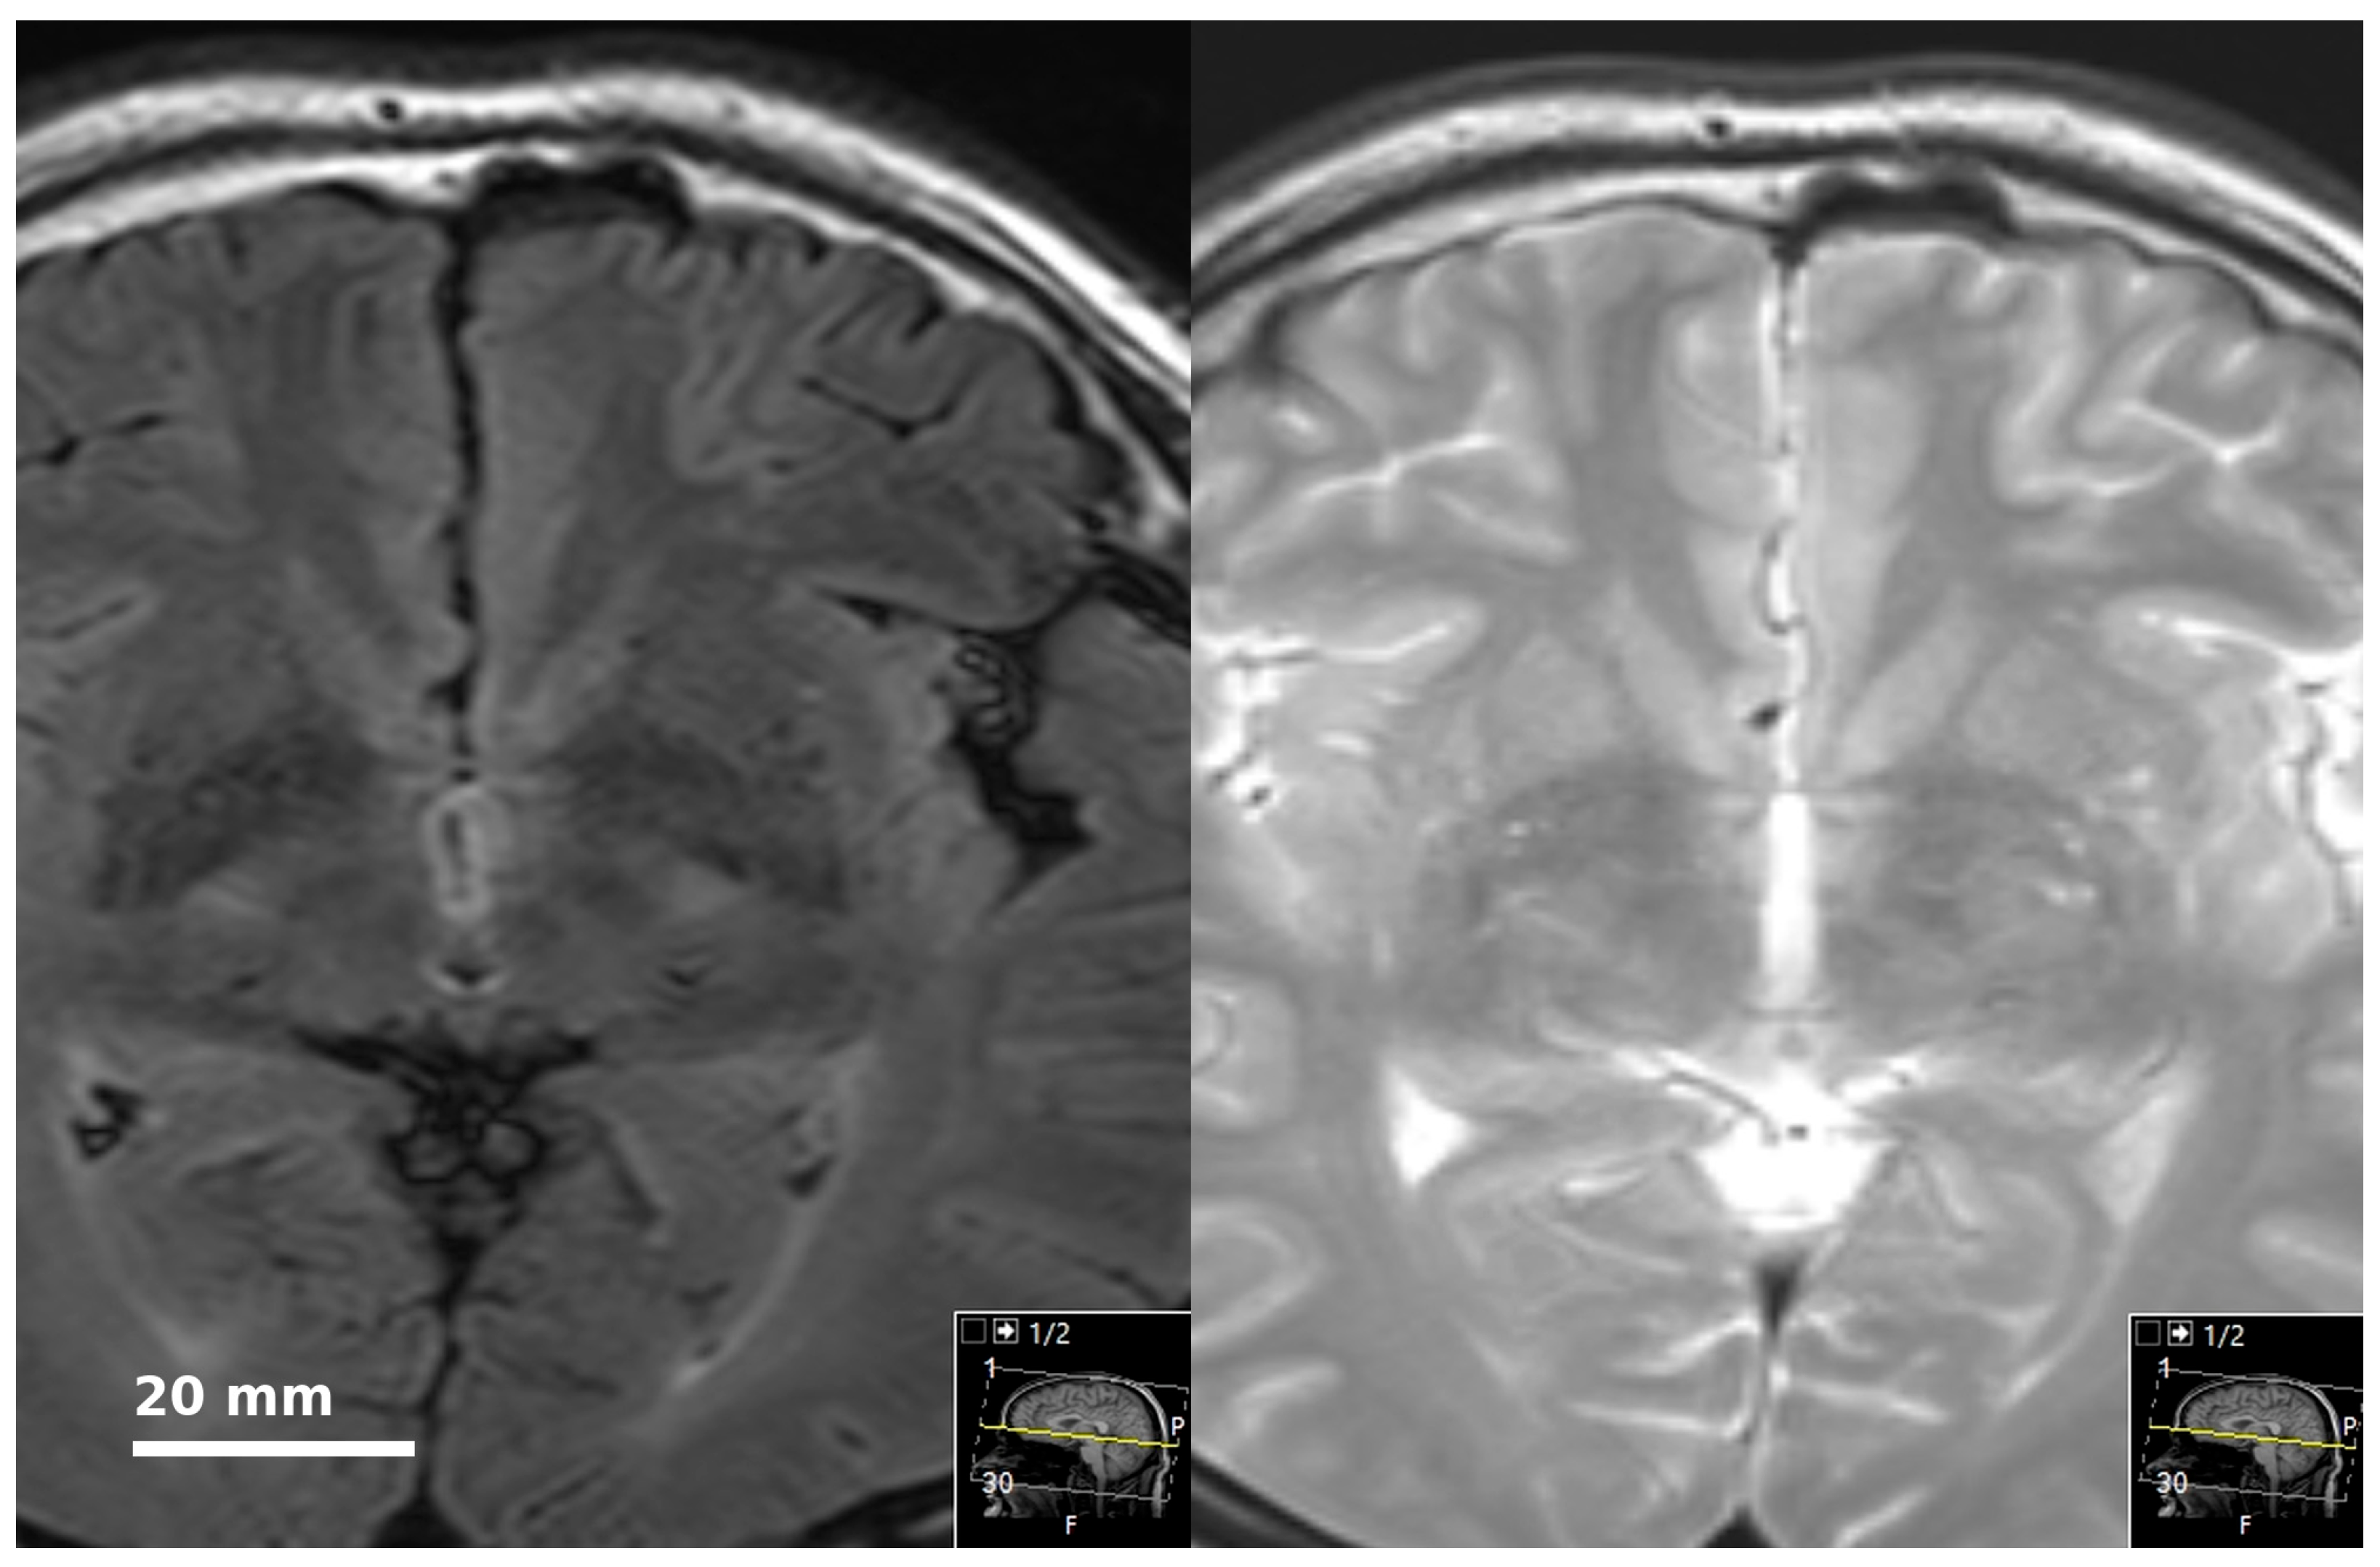

Lesions with an oval or round shape, T1 hypointense, T2 hyperintense, showing signal loss in FLAIR images, showing consistent distribution with periarterial anatomy, and with no hyperintense surrounding rim (suggestive of gliosis) were defined as PVS, as previously described [10].

The PVS score was based on the visual assessment scores indicated in previous studies [1,6,11,12]. PVS scores were calculated separately on each brain side in seven different regions. These regions were: (1) mesencephalon (including upper pons); (2) cerebellum; (3) hippocampus; (4) subinsular region (capsula externa, claustrum, capsula extrema); (5) basal ganglia; (6) frontal lobe; and (7) parieto-occipital lobes. Each region was assessed for the quantity and size of PVS. Thus, in a defined region, 0 PVS scored as 0 points, 1–5 PVS scored as 1 point, 6–10 PVS scored as 2 points, 11 and above PVS scored as 3 points (See Figure 1). In size assessment, the longest diameter of the most prominent PVS determined the size score: PVS <2 mm scored as 1 point; PVS ≥2 mm and <4 mm scored as 2 points; and ≥4 scored as 3 points. Global PVS scores ranging from 0 to 84 points were obtained.

Figure 1. A subject with a PVS score of “2” at the left basal ganglia and “1” at the right basal ganglia.